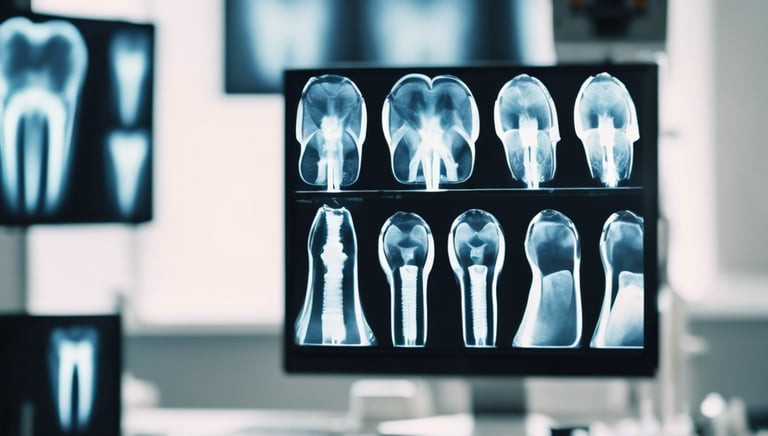

We are a dental office dedicated to serving the community with exceptional oral care in a welcoming environment. With our expertise, cutting-edge technology, and commitment to patient comfort, we strive to provide the best dental experience for our patients.